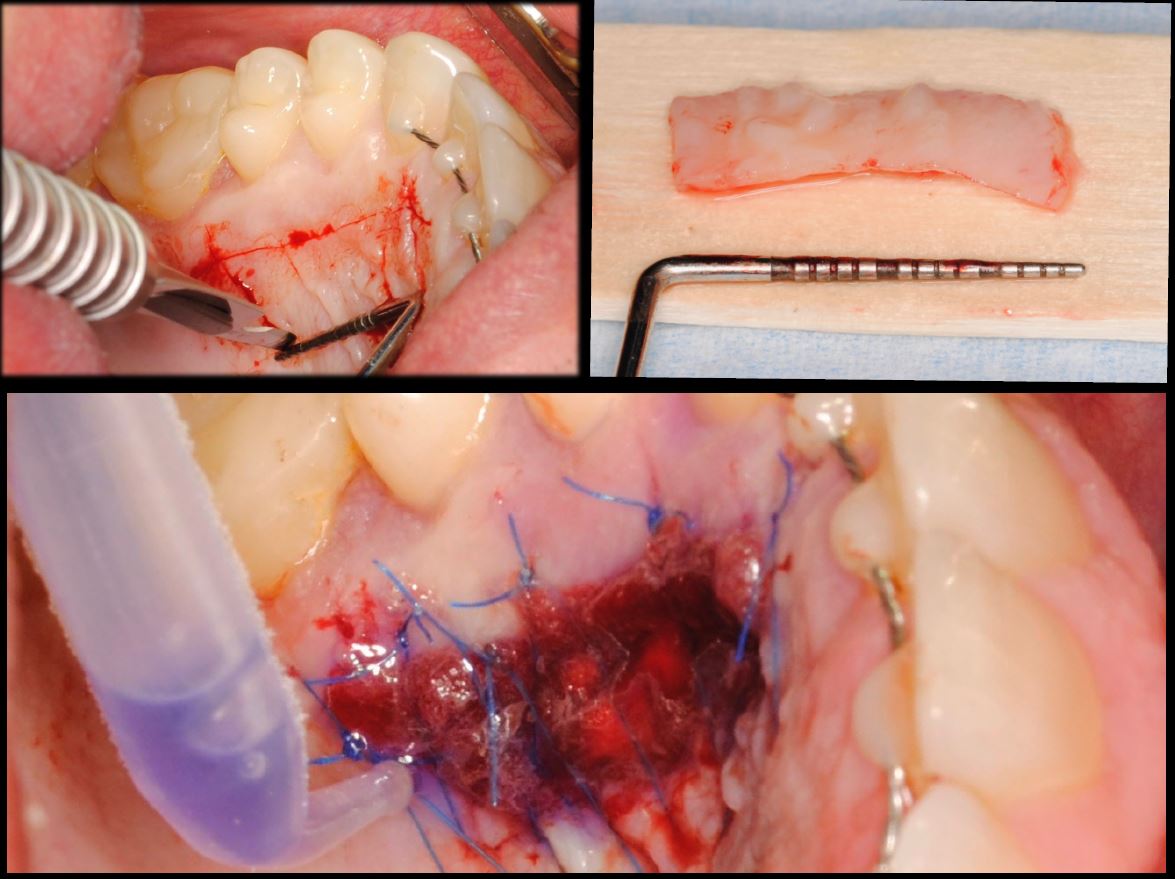

- Injerto de tejido conectivo libre desepitelizado de paladar + Tunelización

Fotografías del proceso: